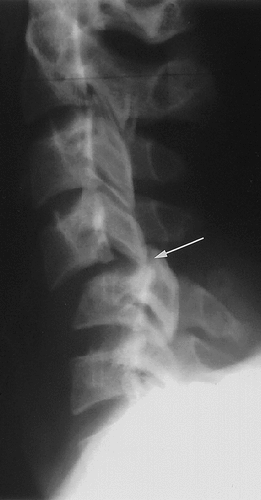

• Hangman fracture or traumatic spondylolisthesis of the axis

• Hyperextension injury

• Virtually never seen in suicidal hanging (usually asphyxial)

• Most commonly seen in major trauma e.g. MCV

• Associated with fracture through bilateral pars interarticularis

• Anterior subluxation of C2 on C3 may be seen (don’t confuse with pseudosubluxation of C2 on C3) - look at posterior cervical line

• Posterior cervical line (line between anterior aspects of spinous processes of C1, 2, and 3) - should line up within 1 mm

• If the posterior cervical line does not overlap anterior aspect of spinous process of C2 by more than 2 mm, true injury is present

• Abnormal posterior cervical line suspect occult hangman fracture of C2

https: //radiopaedia.org/articles/hangman-fracture